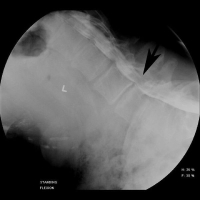

(Click to Enlarge Image) This illustration demonstrates the change in the diameter in the canal in a patient with spinal stenosis. The picture on the right shows the canal wide open with flexion (bending forward). The picture on the left shows significant compression of the nerve sac in the canal (arrow) with backwards bending. Standing and walking require backwards bending, so the symptoms of central stenosis occur with walking and standing.